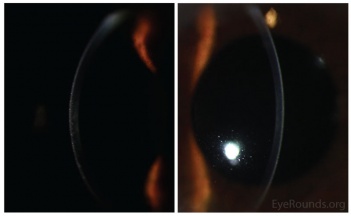

Meesmann Corneal Dystrophy (MECD) is a rare hereditary type of superficial corneal dystrophy that follows an autosomal dominant pattern of inheritance. It is characterized by the bilaterally symmetric development of intraepithelial microcysts that cause fragility of the anterior corneal epithelium. Unlike most other corneal dystrophies, pathology in MECD manifests early in life and epithelial cysts may present already in the first years of life. The onset of symptoms during infancy or early childhood does not become noticeable or problematic until adulthood. As the disorder slowly progresses, the number of tiny epithelial vesicles usually increases with age[3] involving central visual axis and mid-periphery of the cornea[4] and can extend out to the limbus. The bubble-like blebs tend to be denser in the interpalpebral area and can be best visualized with retroillumination[5] Most patients remain asymptomatic or may experience minor symptoms and minimal vision disturbances for years, while some suffer from recurrent episodes of corneal erosions resulting in lacrimation, photophobia, and deterioration in visual acuity, accompanied by irregular astigmatism and subepithelial scarring in some severe cases[3], particularly in elderly patients. Vision is seldom affected to a significant degree.

- Slit-lamp examination in direct illumination: the lesions appear as a variety of different patterns (random, whirled, sectorial, interpalpebral or unilateral and sparing the perilimbal region) of multiple tiny grey dot-like opacities and tiny vesicles in the corneal epithelium, that tend to concentrate in the interpalpebral zone.[10]Fluorescein usually fails to stain the microcysts, as they rarely open to the corneal surface.[11]

- Slit-lamp examination in indirect illumination: the grey opacities appear as multiple solitary, round, and transparent cysts, rarely producing refractile lines due to a coalescence of several cysts[10], while the intervening cornea remains intact or slightly hazy.

- Retroillumination: the intraepithelial microcysts appear as refractile transparent dew drops[11] and the vesicles present isolated.[22] The characteristic bleb pattern of Meesmann corneal dystrophy can be best seen upon retroillumination.[23]